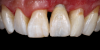

(44.) The provisional restoration was placed back on the implant and tightened to 15 Ncm while applying counter torque. Note that the papillae are partially supported without pressure and that the gingival embrasures are slightly open to allow incisal migration of the papillae during the integration and maturation phase.

Figure 44